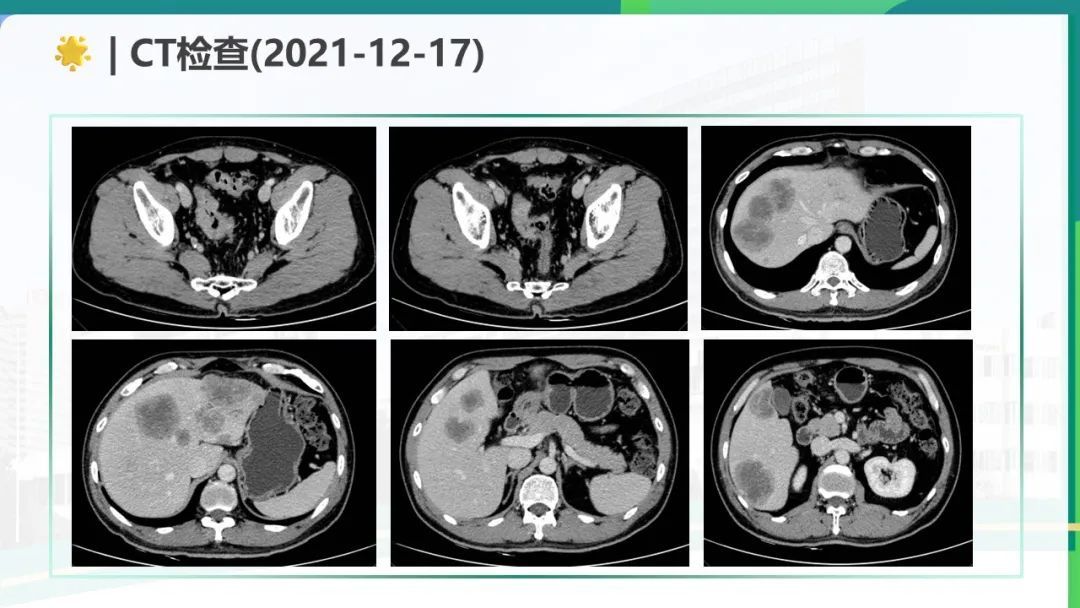

这篇直肠腺癌伴肝转移的MDT病例展示了规范化诊疗流程与多学科协作的重要性,同时也反映了晚期肿瘤治疗的复杂性。1. 初始评估与治疗目标明确性:病例通过肠镜、病理、影像学及基因检测完成了精准分期(cT3cN2M1a IVa期),并基于KRAS突变状态排除了抗EGFR治疗可能。MDT团队在初始不可切除状态下确立了"转化治疗+争取NED"的目标,符合ESMO指南推荐,体现了对治疗预后的科学判断。2. 转化治疗的方案选择与疗效:采用FOLFOXIRI三药化疗联合贝伐珠单抗是高风险结直肠癌转化的标准方案。影像学显示肝转移灶从最大45mm缩小至18mm,直肠壁厚度显著改善,肿瘤标志物CEA从376降至正常范围,证明该方案的高效性。但需注意三药方案的毒性管理(如骨髓抑制、神经毒性)。3. 手术策略的创新性:达芬奇机器人辅助手术实现超低位保肛(距肛门3cm),同时术中超声发现MRI未检出的DLM病灶并完整切除,体现了技术进步对手术精准度的提升。肝转移灶采用"切除+消融"组合策略,符合ESMO对寡转移灶局部治疗的推荐。4. 复发后的全程管理:尽管经历多次进展,团队始终尝试通过更换化疗方案(mFOLFOX6、XELIRI)、局部消融及靶向治疗(呋喹替尼)维持NED状态。二线治疗耐受性差可能提示需要更早引入免疫治疗(如MSI检测阴性后考虑PD-1抑制剂)或参与临床试验。该病例成功的关键在于:规范的MDT决策、积极的转化治疗、精准的手术干预及动态的复发管理,为类似患者提供了有价值的诊疗参考。

该病例中,男,55岁,患者主诉大便性状改变3月余,检查发现肝占位1天。经过一系列的检查,诊断为直肠腺癌并肝转移 cTxN2M1(肝) IV期 RAS野生型 MSS,经过邓权通专家规范治疗,该患者的症状明显改善,疾病的病程也得到了控制。在RAS/BRAF野生型转移性结直肠癌(mCRC)患者中,西妥昔单抗联合FOLFOXIRI(奥沙利铂+伊立替康+氣尿嘧啶)相比单纯化疗方案(如FOLFOX或FOLFIRI),可显著延长无进展生存期(PFS)和总生存期(OS)。肝转移转化治疗:中国FOCULM研究证实,改良FOLFOXIRI联合西妥昔单抗可将RAS/BRAF野生型结直肠癌肝转移患者的无疾病证据(NED)转化率显著提高,为初始不可切除患者创造手术机会。